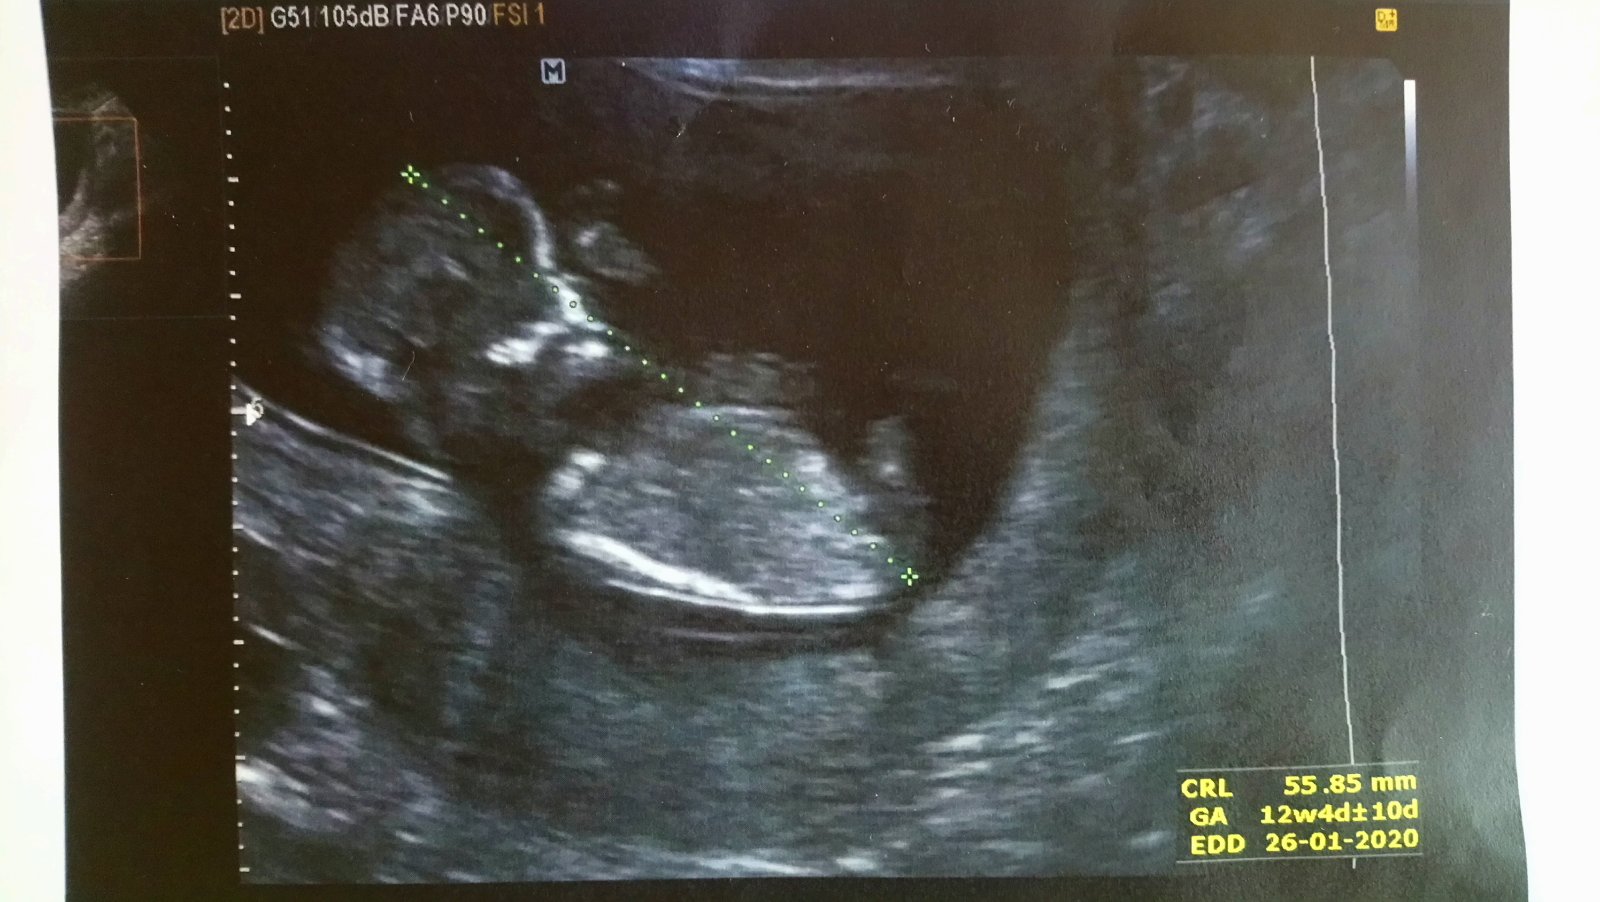

Zatím jen tato... Vím, že je brzo, ale ta zvědavost je strašná věc :D

@lopinka81 fotka je z 12+4 tt. Teď jsem v 16 tt a o fotku jsem si neřekla 😞 A další kontrola za 3tt...